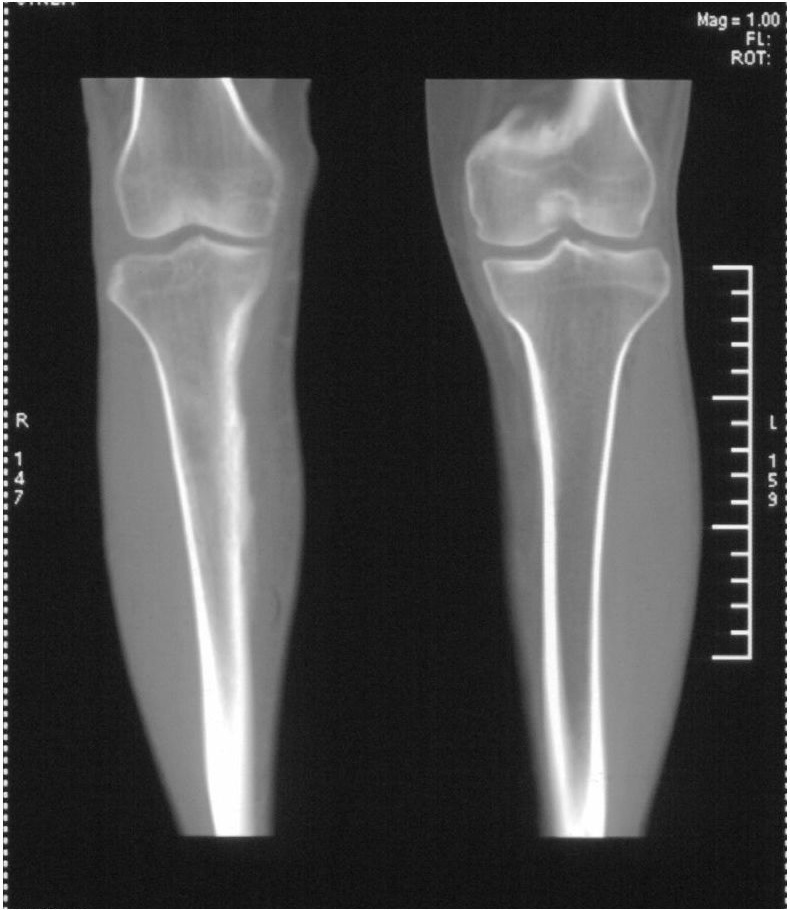

髓腔密度呈絮状增高,胫骨上端内侧可见层状骨膜反应,考虑骨髓炎.

髓腔密度呈絮状增高,胫骨上端内侧可见层状骨膜反应,肌间隙模糊,考虑骨髓炎.

破坏、增生、骨膜反应,考虑骨髓炎